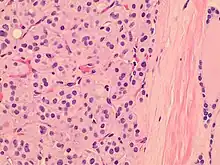

| Histopathology of a Hürthle cell adenoma | |

Hürthle cells are characterized as enlarged epithelial cells. These cells, when stained with hematoxylin-eosin show as pink. This is due to the abundant mitochondria and granular eosinophilic matter within the cells' cytoplasm. These cells are often found in the thyroid. The thyroid is a butterfly-shaped organ, responsible for producing various hormones for metabolism. These cells are often benign, but they can be malignant and metastasize. Hürthle cells are resistant to radiation, but can be treated using radioactive iodine treatment.[4]